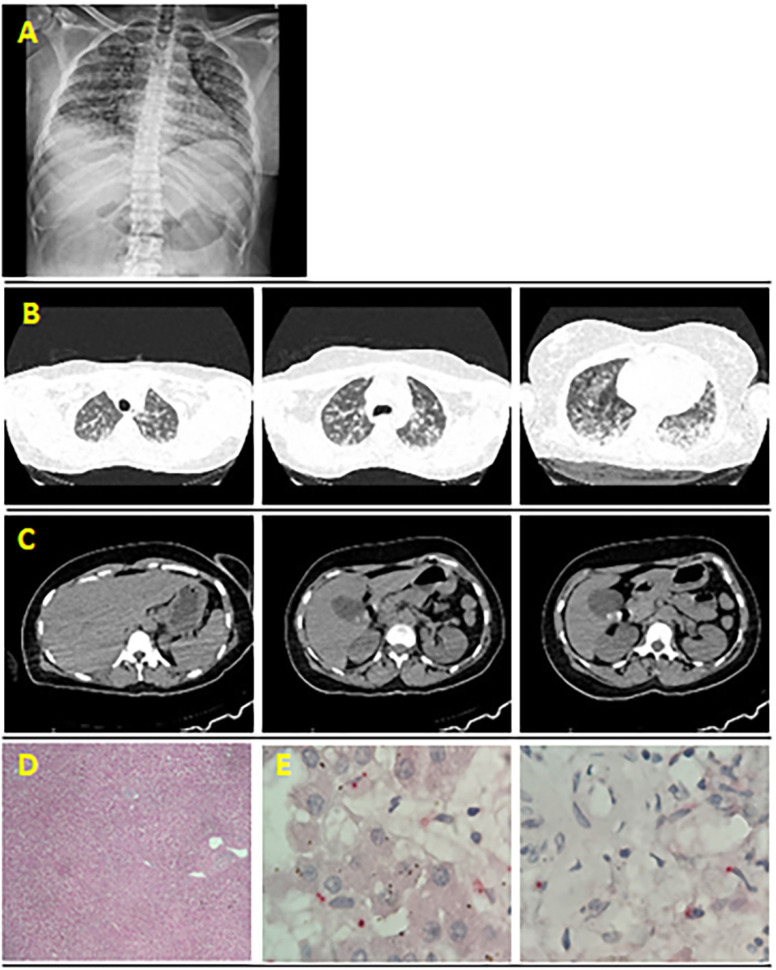

Coinfection with leptospirosis and other infectious agents pose major challenges in medical practice, often due to difficulties in isolating these agents, symptoms overlap, and lack of specific investigation protocols in areas with emerging and re-emerging diseases. Consequently, knowledge regarding these coinfections and their impact on clinical outcomes are limited. A previously healthy 33-year-old woman, with no history of chronic or malignance diseases, was admitted with febrile icteric illness, pulmonary hemorrhage, acute kidney injury, thrombocytopenia, and shock. Leptospirosis, COVID-19, human rhinovirus, and dengue in the acute phase were clinically and pathologically diagnosed. Multiple coinfections can rapidly lead to multiple organ and system failure, often resulting in a fatal outcome.